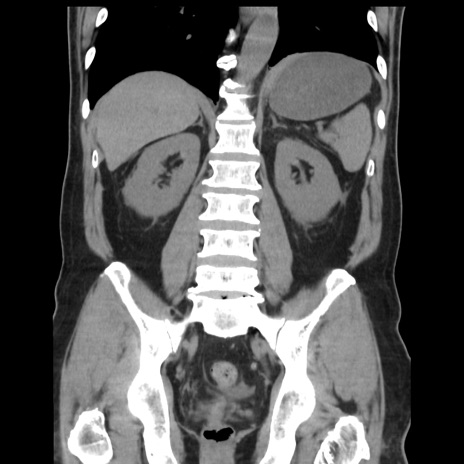

症例16(冠状断像)

【症例】 70歳代男性

【主訴】 腹痛、嘔吐

【現病歴】 約1ヶ月前より間欠的に腹痛と嘔吐あり、当院消化器内科を受診したところCTで多発する肝臓のLDAを指摘され、精査中であった。以降は消化器症状は安定していたが、2日前より嘔気と腹痛があり、同日より排便・排ガスが消失した。改善認めず、 本日、救急外来を受診した。

【既往歴】 大腸ポリープ切除後。

【身体所見】意識清明・会話良好、BT 36.3℃、BP 127/80mmHg、 P 80bpm、腹部:膨満あり、平坦・軟、上腹部正中および下腹部正中に圧痛あり、反跳痛なし、筋性防御なし。

【データ】WBC 7200、CRP 0.77